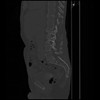

7 CUERPO,CE,Sagittal,3.000,CUERPO,Sagittal,